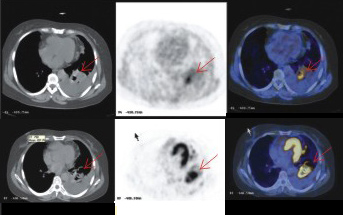

5、 療效的評估與全身監(jiān)測

由于PET-CT顯像屬于全身顯像,因而對治療后療效評估(包括:手術(shù)腫瘤殘留情況或復(fù)發(fā)與疤痕組織的鑒別、放療和化療前后腫瘤病灶的變化、放射性肺炎和腫瘤復(fù)發(fā)的鑒別等)提供可靠的依據(jù)。

PET-CT可準(zhǔn)確的對心肌缺血情況和心肌活力進(jìn)行評估,有助于冠心病的早期診斷,冠心病嚴(yán)重程度判斷及心臟手術(shù)療效評估。CT與PET的功能代謝顯像相結(jié)合,近乎完美地實(shí)現(xiàn)了心臟機(jī)構(gòu)、功能、代謝的同步顯示和評價(jià)的目的。臨床具體應(yīng)用于:冠心病早期診斷和心肌血供評價(jià);鑒別心肌梗塞區(qū)活性與無活性心肌;冠狀動(dòng)脈血管重建后心肌灌注、代謝和功能恢復(fù)的評價(jià);不穩(wěn)定性心絞痛的診斷及心肌病的心肌損傷評價(jià)。

(上)13 N-NH3心肌灌注顯像,(下)18F-FDG心肌代謝顯像。結(jié)論 兩種顯像不匹配,示心肌部分存活